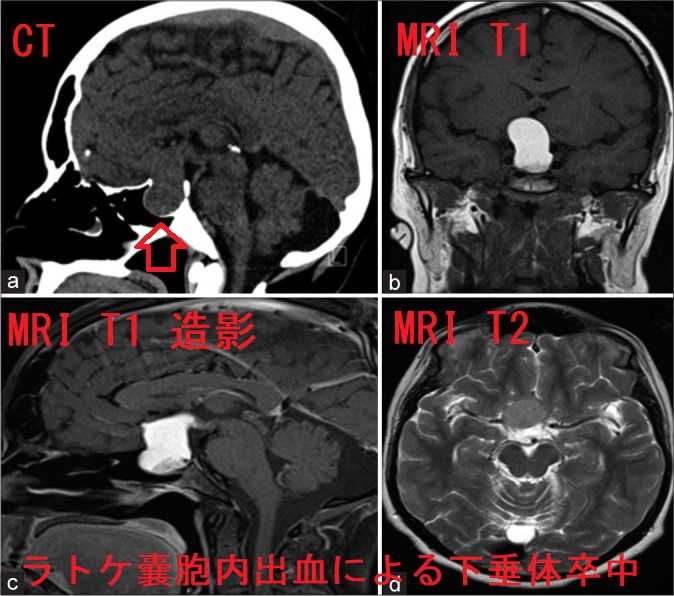

ラトケ嚢胞内出血(ラトケのう胞内出血)による下垂体卒中[Surg Neurol Int. 2021 Oct 6;12:504.]

- ラトケ嚢胞(ラトケのう胞)内で出血すると下垂体卒中をおこし[内分泌エマージェンシー下垂体卒中]、準緊急手術になる事があります。(Oper Neurosurg (Hagerstown). 2020 May 1;18(5):470-479.)(第54回 日本甲状腺学会 P052 ラトケ嚢胞卒中による汎下垂体機能低下症にバセドウ病を合併し,周術期管理を行った1例)

下垂体腺腫(下垂体神経内分泌腫瘍)による下垂体卒中よりも軽度とされます[Surg Neurol Int. 2021 Oct 6;12:504.]